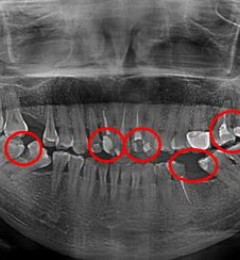

湛江致美口腔补牙修复牙 呵护口腔健康您的不二之选

蛀牙,医学上称龋齿。它是细菌性疾病,可以继发牙髓炎和根尖周炎,甚至能引起牙槽骨和颌骨炎症。如不及时治疗,病变继续发展,形成龋洞,终至牙冠完全破坏消失,其发展的最终结果是牙齿丧失。...【浏览全文】